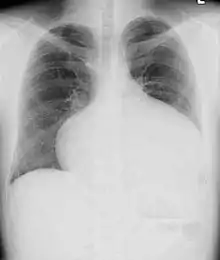

Adults with an uncorrected ASD present with symptoms of dyspnea on exertion (shortness of breath with minimal exercise), congestive heart failure, or cerebrovascular accident (stroke). They may be noted on routine testing to have an abnormal chest X-ray or an abnormal ECG and may have atrial fibrillation. If the ASD causes a left-to-right shunt, the pulmonary vasculature in both lungs may appear dilated on chest X-ray, due to the increase in pulmonary blood flow.[34]